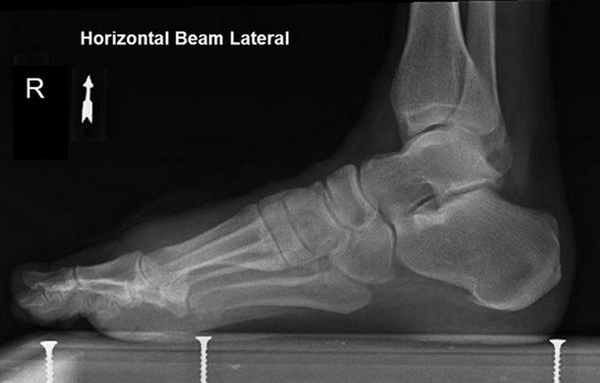

В первую очередь показано выполнение рентгенографии с нагрузкой в прямой и боковой проекции. При этом в прямой проекции выявляется неполное покрытие суставной поверхности головки таранной кости ладьевидной костью, увеличенный угол между таранной костью и первой плюсневой костью (угол Simmon), что встречается со 2 А стадии.

На боковых рентгенограммах определяется увеличенный таранно-плюсневый угол (угол Meary >4° свидетельствует о плоской стопе). Также снижается угол высоты пяточной кости (в норме 17-32°).

На 3-4 стадиях определяются признаки подтаранного артрита, на 4 стадии появляется картина подвывиха таранной кости в голеностопном суставе.